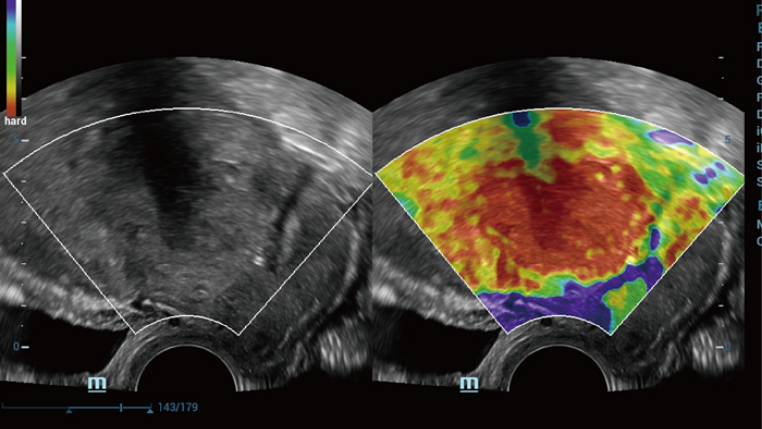

Advanced Features